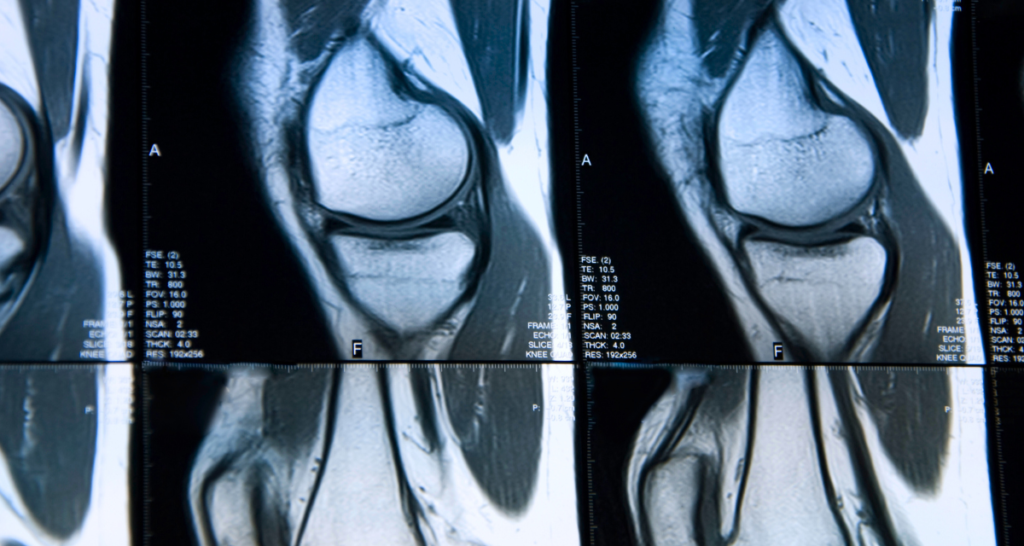

Joint MRI

Shoulder, knee, and hip MRIs often reference ligaments, tendons, cartilage, and fluid. Small tears or inflammation can be common, especially for active individuals.